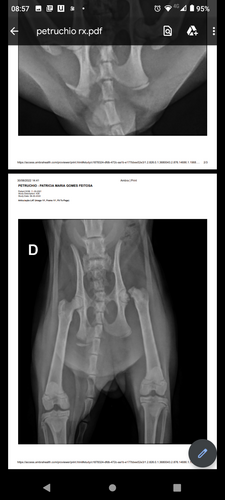

Olá pessoal estamos fazendo está vaquinha para ajudar o petruchio um gatinho de 7 meses que foi atropelado dia 29/06/22. O mesmo foi levado ao veterinário a clínica são Bernardo e lá deram os primeiros socorros,e precisou fazer raio-x a dona dele que é minha amiga/vizinha chamada Patrícia não tem condições tirou dinheiro do aluguel para pagar a consulta na clínica o raio-x ela consegui ajuda de uma moça! Mas ele vai precisar fazer cirurgia pois quebrou o fêmur estamos arrecadando dinheiro para fazer essa cirurgia nele! Quem quiser ir ver, ou fotos entrar em contato vou deixar o celular dela aqui 16 992854065 (Patrícia) e se quiser falar comigo este é o meu 16 992665825!